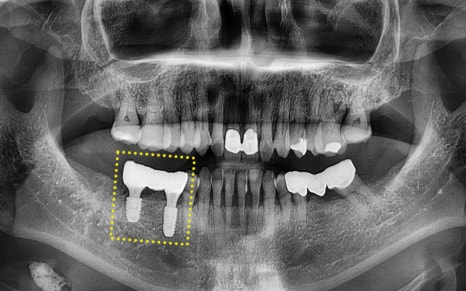

양쪽 아래 어금니에

통증을 느끼고 계셨고,

파노라마 사진을 촬영해

정밀하게 상황을 체크해보았습니다.

🦷 내원 당시 상태 요약

✔ 우측 아래 첫번째 큰 어금니는

이미 발치된 상태

✔ 우측 아래 두번째 큰 어금니는

치아 파절로 보존 어려워 발치 결정

✔ 두번째 작은 어금니는

기존에 크라운이 씌워져 있었고,

두번째 큰 어금니와

연결된 브릿지 상태였음

✔ 좌측 아래 사랑니는

염증으로 인해 발치 필요